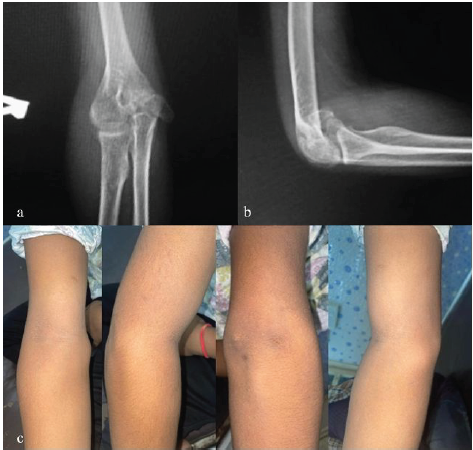

(K-Wire with cannulated cancellous [CC] screw) A 15-year-old male sustained an injury while playing cricket following a fall on his outstretched arm. Examination revealed medial swelling, tenderness, and valgus instability, with radiographs confirming a malunited medial epicondyle fracture. Open reduction was performed via a medial approach. Osteotomy was done using a K-wire for temporary stabilization and a CC screw for definitive fixation. At 12 weeks, radiological union was achieved with elbow range of motion (ROM) of 0–130° and no residual instability (Figs. 1 and 2).

Figure 1: Pre-operative right elbow X-rays and clinical pictures (a) X-ray right elbow anterior-posterior view, (b) X-ray right elbow lateral view, (c) clinical pictures of right elbow.